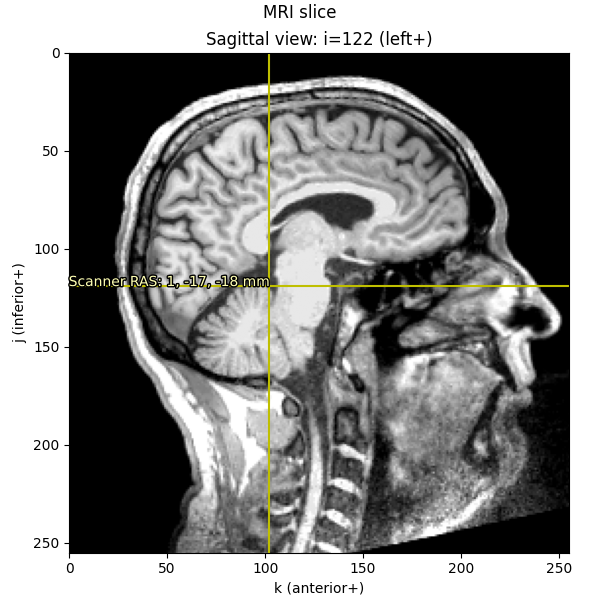

Let’s write a short function to visualize where our voxel lies in an image, and annotate it in RAS space (rounded to the nearest millimeter):

def imshow_mri(data, img, vox, xyz, suptitle):

"""Show an MRI slice with a voxel annotated."""

i, j, k = vox

fig, ax = plt.subplots(1, figsize=(6, 6), layout="constrained")

codes = nibabel.orientations.aff2axcodes(img.affine)

# Figure out the title based on the code of this axis

ori_slice = dict(

P="Coronal", A="Coronal", I="Axial", S="Axial", L="Sagittal", R="Sagittal"

)

ori_names = dict(

P="posterior", A="anterior", I="inferior", S="superior", L="left", R="right"

title = ori_slice[codes[0]]

ax.imshow(data[i], vmin=10, vmax=120, cmap="gray", origin="lower")

ax.axvline(k, color="y")

ax.axhline(j, color="y")

for kind, coords in xyz.items():

annotation = "{}: {}, {}, {} mm".format(kind, *np.round(coords).astype(int))

text = ax.text(k, j, annotation, va="baseline", ha="right", color=(1, 1, 0.7))

text.set_path_effects(

[

path_effects.Stroke(linewidth=2, foreground="black"),

path_effects.Normal(),

]

# reorient view so that RAS is always rightward and upward

x_order = -1 if codes[2] in "LIP" else 1

y_order = -1 if codes[1] in "LIP" else 1

ax.set(

xlim=[0, data.shape[2] - 1][::x_order],

ylim=[0, data.shape[1] - 1][::y_order],

xlabel=f"k ({ori_names[codes[2]]}+)",

ylabel=f"j ({ori_names[codes[1]]}+)",

title=f"{title} view: i={i} ({ori_names[codes[0]]}+)",

fig.suptitle(suptitle)

return fig

imshow_mri(data, t1, vox, {"Scanner RAS": xyz_ras}, "MRI slice")

Notice that the axis scales (i, j, and k) are still in voxels

(ranging from 0-255); it’s only the annotation text that we’ve translated

into real-world RAS in millimeters.